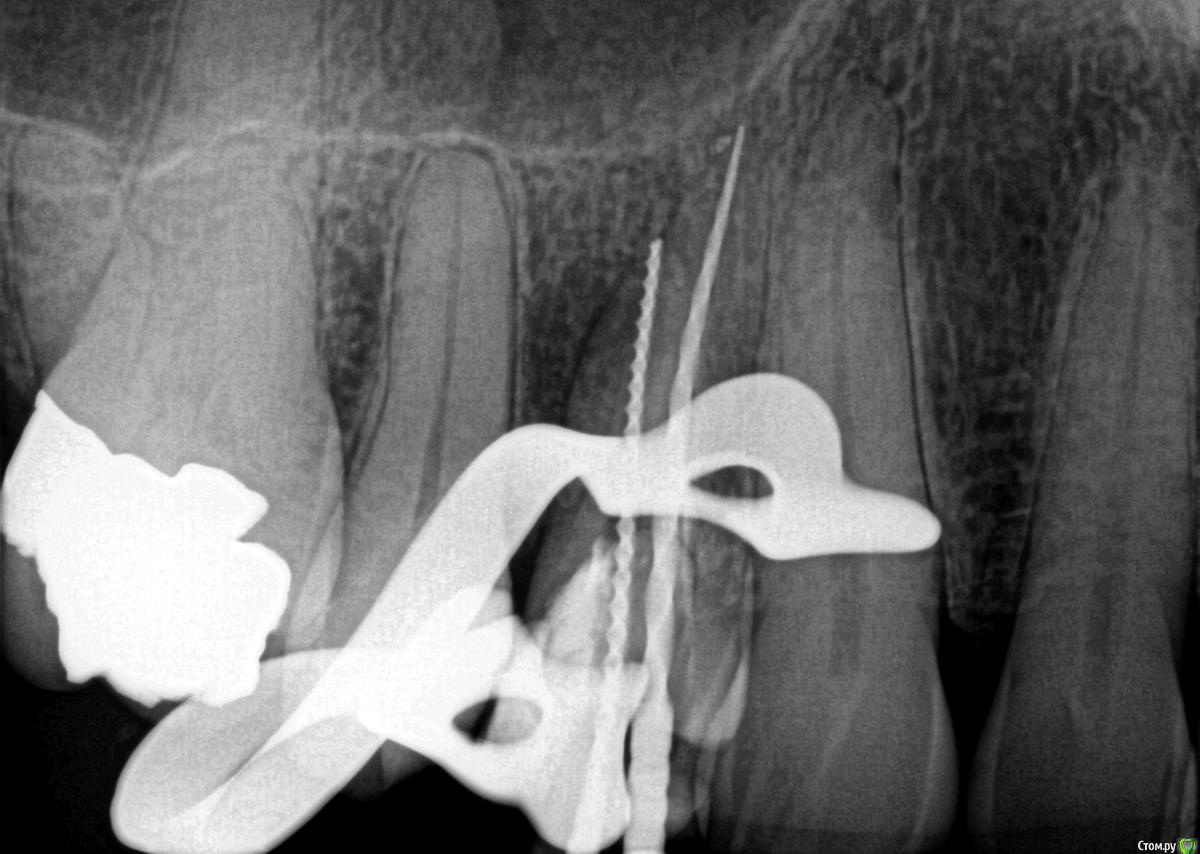

Rim3 Опубликовано 1 декабря, 2015 Поделиться Опубликовано 1 декабря, 2015 Уважаемые стоматологи, помогити пожалуйста! Во время пломбировки каналов верхнего бокового зуба с правой стороны у меня возникла резкая боль в районе синуса. Боль ушла через 3 -5 минут и врач настоял на продолжении лечения. Далее у меня опухла вся щека и появились синяки под глазами и щекой. Мне назначили стероиды и антибиотики. Как я позже поняла это было выведение гипохлорита натрия за пределы корня и травма. Теперь опухоль спала и синяки прошли. Я еще очущаю дискомфорт и некую болезненность в этой области.У меня теперь возник вопрос по поводу качества проведенного лечения каналов. Я собиралась закрыть зуб коронкой, но теперь сомневаюсь. Как вы считаете глядя на снимки, качественно ли запломбированы каналы? Что если не только гипохлотит натрия, но и гутаперча вышла за пределы корня. Возможны ли осложнения в будущем и операция по удалению лишнего материала? Ссылка на комментарий